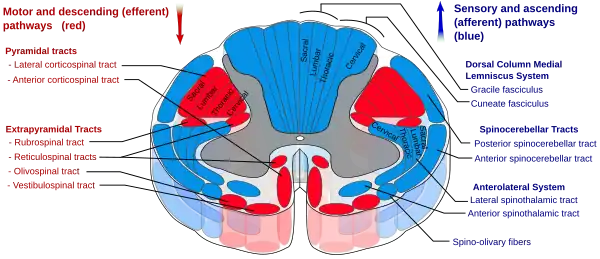

- Corticospinal tract - the "pyramidal" tract containing upper motor neurons mediates voluntary movements of skeletal muscle. It consists of two subdivisions: the lateral corticospinal tract which is situated in the lateral funiculus, controls musculature associated with the limbs and does not decussate within the spinal cord; and the anterior corticospinal tract which is situated in the anterior funiculus, controls the musculature of the trunk and does decussate within the spinal cord.

- Posterior funiculus - posterior anatomical division of the white matter of the spinal cord exclusively containing axons of 1st-order neurons of the dorsal column–medial lemniscus pathway which conveys sensory stimuli regarding fine (discriminative) touch, proprioception, and vibratory sense from the trunk and limbs. These do not decussate within the spinal cord.

- Spinothalamic tract - consists of two subdivisions: the lateral spinothalamic tract which is situated within the lateral funiculus and conveys sensory stimuli regarding pain, temperature, and pressure; and the anterior spinothalamic tract which is situated within the anterior funiculus and conveys sensory stimuli concerning crude (non-discriminative) touch and pressure information. Both tracts decussate within the spinal cord.

At the level of the lesion, destruction of the anterior gray column and potentially also of the anterior (motor) root of the corresponding spinal nerve results in destruction of lower motor neurons of the spinal segment on the affected side, causing flaccid paralysis and consequent muscle atrophy of the corresponding myotome.[5]

Disruption of the upper motor neuron corticospinal tract produces ipsilateral spastic paralysis below the level of the lesion.[2][4] Spasticity is a consequence of disruption of ipsilateral extrapiramidal tracts.[5]

Disruption of the dorsal column pathway causes ipsilateral loss of fine (discriminative) touch, vibration, and proprioceptive perception.[4]

Disruption of the spinothalamic tract causes contralateral loss of pain, temperature, and crude (non-discriminative) touch sensation loss starting from 2-3 spinal cord segments inferior to the level of the lesion (because 2nd-order axons of the spinothalamic tract decussate obliquely).[5]